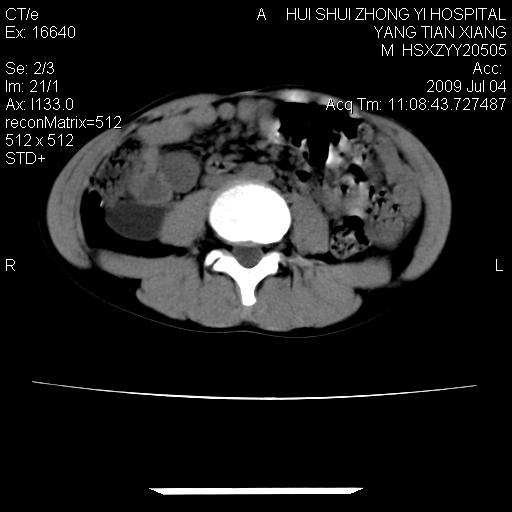

肝右叶胆管内见条状高密度影,脾脏增大,双肾上腺无异常;右肾正常结构消失,其实质内见类圆形低密度灶,ct值范围0-6hu,界清,右输尿管全程伴行多发低密度灶,界清,膀胱壁增厚,腹盆腔未见确切肿大淋巴结。

考虑:1、肝内多发胆管结石并肝内胆管扩张。2、右肾、输尿管多发脂肪瘤,多发平滑肌瘤?建议ct增强检查。4、膀胱壁增厚。

右侧巨输尿管可能。

膀胱壁增厚。

2、右侧巨输尿管并右肾积水可能性大。

右侧巨输尿管并神谕积水,左肾代偿性肥大,脾大,肝内胆管多发结石并胆管扩张。